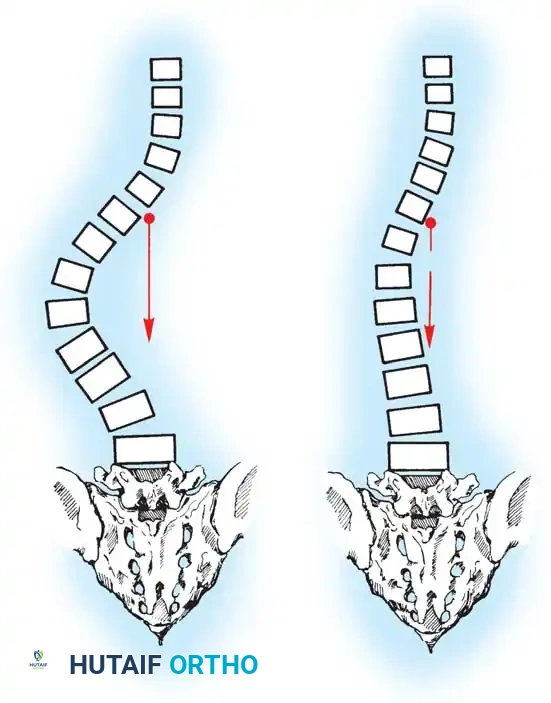

Biomechanics of Bone Grafting

Bone graft incorporates most effectively under compressive loads and is biologically disadvantaged in environments of distraction. Therefore, in scoliosis correction, if autogenous bone is limited, it should be preferentially concentrated on the concave side of the curve, which is subjected to compressive forces, rather than the convex side, which experiences tension. Furthermore, the farther the fusion mass is placed from the instantaneous axis of rotation, the more effectively it will neutralize movement across that axis.